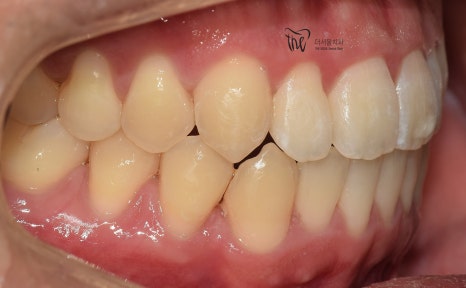

정면 및 측면에서 봤을 때, 측절치의 후방위치에

따라서 반대교합 형태를 보여주고 있으면서

이 때문에 송곳니가 더 덧니처럼 보여지는 느낌을

받고 있는 모습을 볼 수 있습니다.

나아가, 하악의 전치부 쪽에도 총생 현상이

같이 관찰이 되면서 이런 비심미적인 요소들을

개선시키고 싶은 마음으로 더서울치과에

내원하셨던 분입니다.